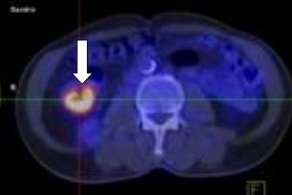

Hình ảnh khối đại tràng phải, kích thước 3x4 cm. Ảnh: BVCC. |

Sau khi kiểm tra, sinh thiết, các bác sĩ chẩn đoán bệnh nhân bị ung thư biểu mô tuyến đại tràng phải, di căn hạch ổ bụng, di căn gan, phổi.

Sau 6 tháng điều trị, bệnh đáp ứng một phần, các tổn thương u nguyên phát, di căn hạch ổ bụng, phổi đã không còn. Tuy nhiên, tổn thương di căn gan vẫn tồn tại và kích thước đã thuyên giảm.